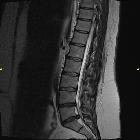

Disc protrusions are a type of disc herniation characterized by protrusion of disc content beyond the normal confines of the intervertebral disc, over a segment less than 25% of the circumference of the disc. The width of the base is wider than the largest diameter of the disc material which projects beyond the normal disc margins. The protrusion must not extend above or below the relevant vertebral endplates .

A disc protrusion is also described in terms of its axial position, into central, subarticular, foraminal, extraforaminal, or anterior locations .

A disc extrusion is distinguished from a disc protrusion in that the base of the protruded disc material is narrower than its 'dome'. Furthermore, this material may extend above or below the disc level.